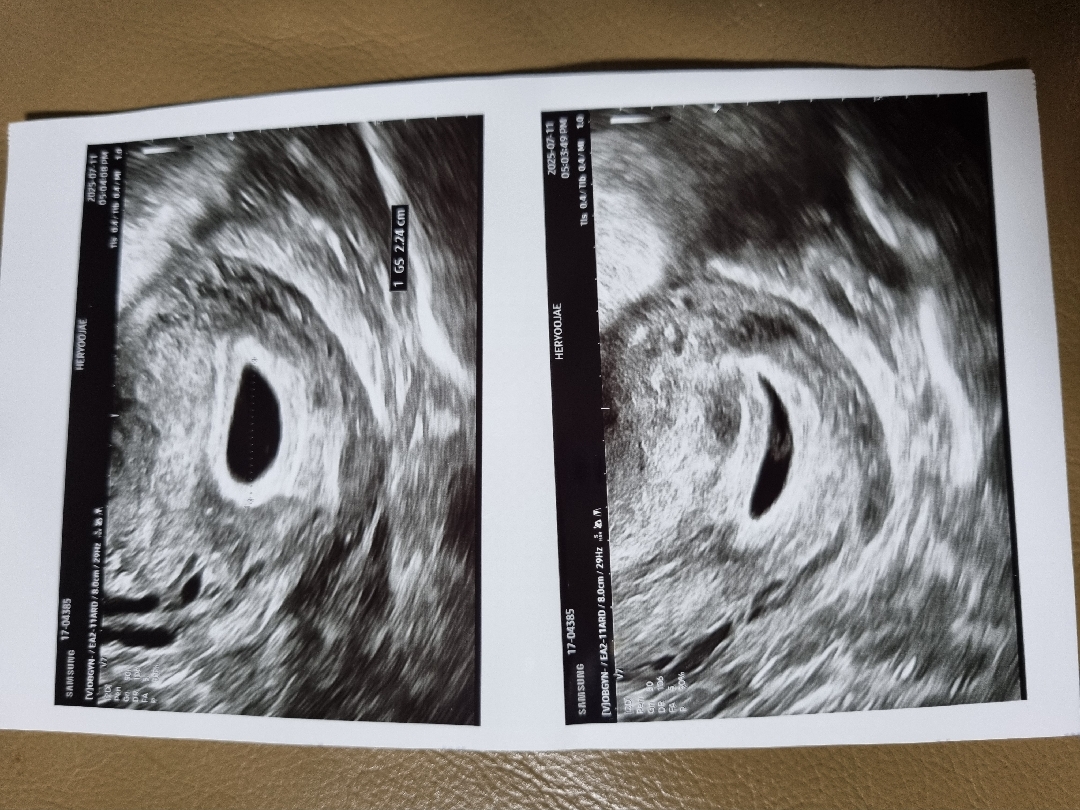

5주차때춈파사진인데좀봐주세요

다른분들처럼똥그랗게이쁘지도않고 난항도조금 다이아처럼안보이는거같구.. 아가는잘크고있는건지 자꾸배가아픈데 5주때선생님은신경쓰지말라고 자궁커지려고한다고해서. 그려러니..하려해도너무불안하고 2주뒤에보자는데 2주는넘길고..시간도안가고..지금일주지났는데..ㅠㅠ미티것어요 저저벌달에화유하고 몇년전에계유하고 했던기억에...너무불안하고 힘드네요 입덧약먹어도이놈에 입덧은 그칠줄모르고 또괜찮아지면불안하고..에휴..